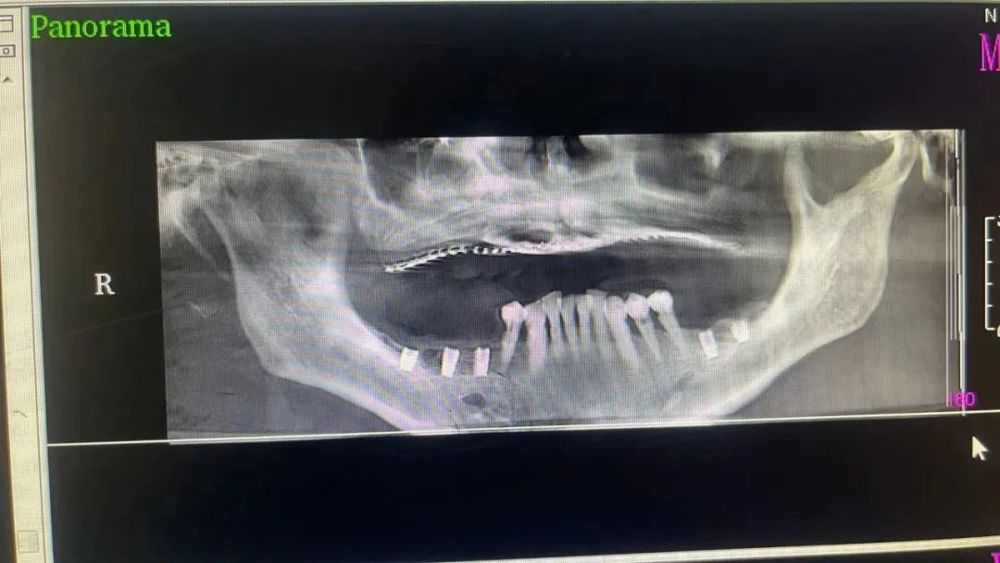

案例二

种植前 种植后